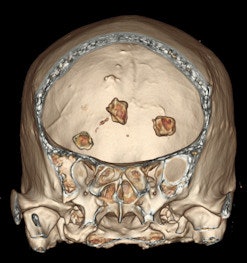

Because of its multiplanar reconstruction and 3D reconstruction capabilities, CT has supplanted the use of skull x-rays in the diagnosis of intracranial pathology. Also, CT is better than MRI in identifying and characterizing intracranial calcification, although newer MRI sequences are promising. In certain clinical situations, neurological symptoms correlate better with MRI findings than with the corresponding CT-identified calcifications.

The superiority of CT over x-ray in detecting macroscopic intracranial calcifications has resulted in routine visualization of various forms and sizes of brain stones. Despite the ability of CT to quantify calcification, the subjective designation of intracranial calcifications as brain stones has been considered of less importance lately, they added.

Macroscopic calcifications are present in meningiomas in up to 60% of cases, the pattern of which may range from diffuse, rim, or sand-like to focal or even globular. Calcified meningiomas can be associated with focal thickening of the overlying skull bones or with dilatation of the adjacent air-containing sinus of the skull base, they stated.